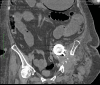

This case report evaluates current diagnostic and treatment approaches for intrapelvic acetabular migration, focusing on the rare but serious complication of acute limb ischemia following hip arthroplasty. A 67-year-old female with a history of total hip arthroplasty 10 years ago presented with acute limb ischemia after experiencing a traumatic event 72 hours prior, which had caused displacement of her hip prosthesis. Notably, she had a history of a traumatic event two years earlier for which she had been advised to undergo surgical correction, which she had refused. A multidisciplinary team assessed her preoperatively. She was diagnosed with SVS III irreversible acute limb ischemia due to compression of the external iliac artery from the prosthesis migration, prompting an emergency hip disarticulation. The patient successfully underwent hip disarticulation and mechanical thrombectomy of the external iliac artery using a Fogarty catheter. Postoperative recovery was notable, with significant pain relief, improved mental status, and restoration of the iliac pulse. Early diagnosis and management of acute arterial injury are crucial to preventing severe outcomes. This report highlights the importance of timely intervention to mitigate limb-threatening and life-threatening complications. It underscores the need for vigilant monitoring during hip replacements and the effectiveness of a multidisciplinary approach in complex cases. Continued research is essential to enhance diagnostic and therapeutic strategies for this rare yet critical complication and to improve overall patient outcomes.